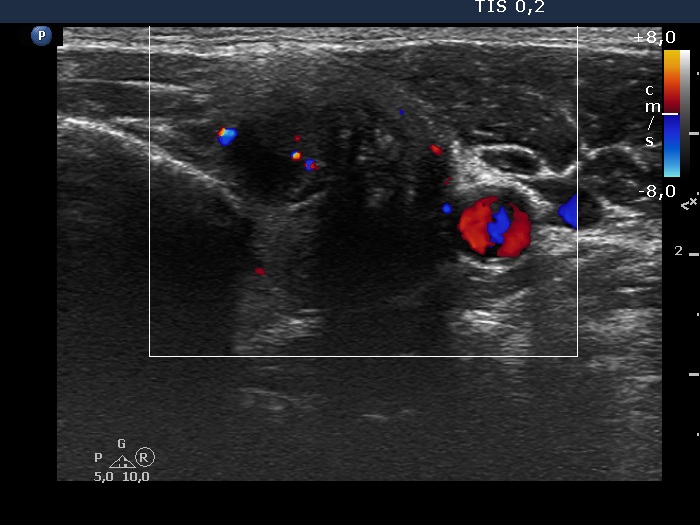

Left lobe, transverse scan, color Doppler mode. The vascularization is not specific.